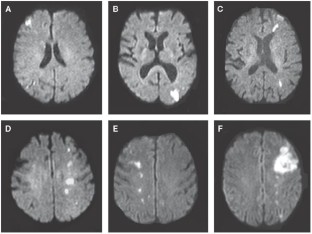

Szabo K et al. (2001) Acute stroke patterns in patients with internal carotid artery disease: a diffusion-weighted magnetic resonance imaging study. Stroke 32: 1323–1329

Kim SJ et al. (2006) Acute-stage evolution of watershed infarction assessed on diffusion-weighted MR imaging. Cerebrovasc Dis 21: 357–362

Chaves CJ et al. (2000) Diffusion- and perfusion-weighted MRI patterns in borderzone infarcts. Stroke 31: 1090–109649